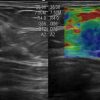

Ung thư tuyến vú

Ung thư tuyến vú - Ảnh 4

» Thông tin: Nữ giới – 45 tuổi.

» Lâm sàng: Kiểm tra sức khỏe.